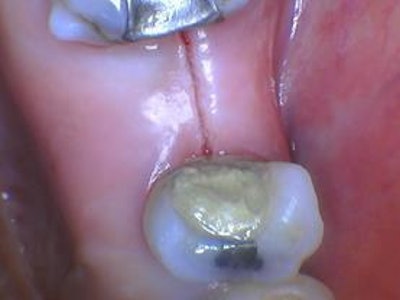

For treatment, the practitioner used a Solea laser (Convergent Dental) on the "hard and soft tissue" setting with the cutting speed controlled with the rheostatic foot pedal. The patient was anesthetized with 1.7 mL of articaine 4% with epinephrine 1:100,000 and 1.8 mL of bupivacaine 0.5% with epinephrine 1:200,000.

The initial scalpel-like incision (figure 4) was made along the crest of the edentulous ridge. The flap incision was around teeth #3 and #5, severing the periodontal attachment, while not touching the adjacent tooth.